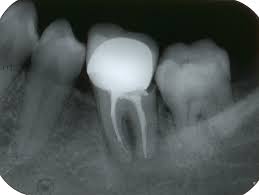

Дан оралног здравља

Обележава се